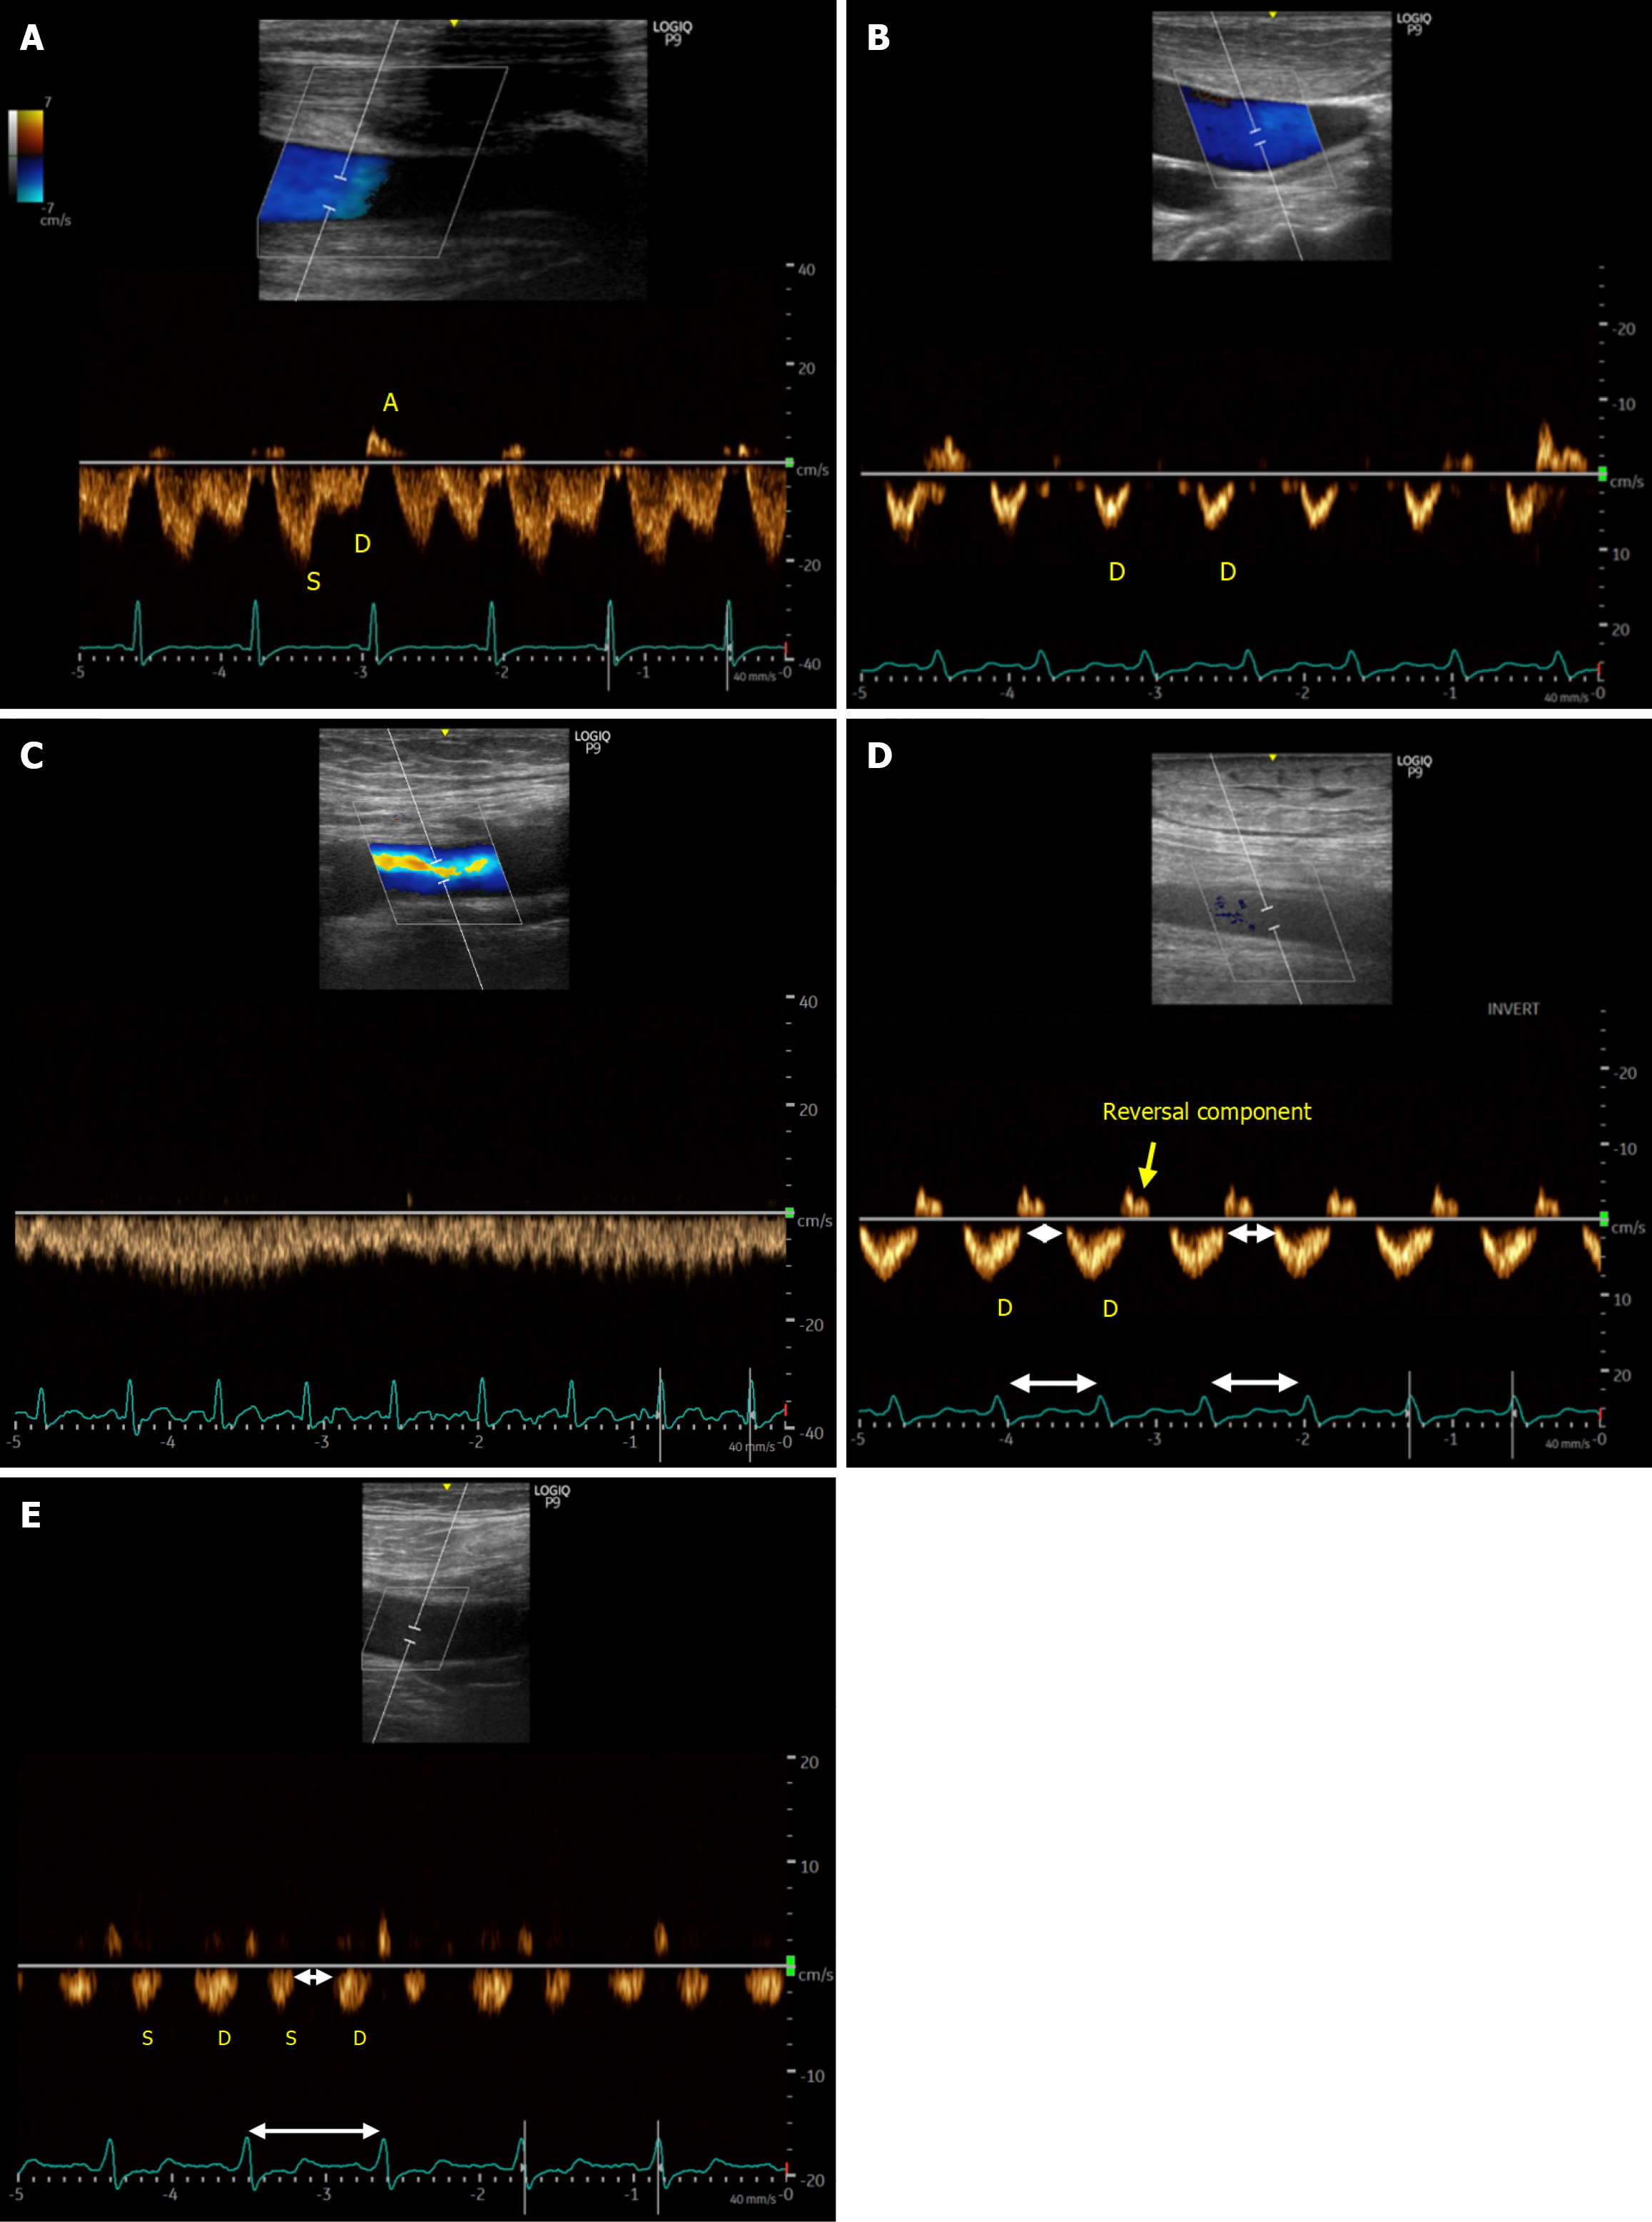

Figure 3 Internal jugular and femoral vein Doppler patterns across congestion states.

A and B: Doppler waveforms of the internal jugular vein showing a normal pattern (A) and a severely abnormal pattern (B). In the normal waveform, the systolic wave is greater than the diastolic (D) wave. In the abnormal pattern, the systolic wave disappears, leaving only a prominent D-wave below the baseline, indicating flow toward the heart in diastole; C and D: Normal femoral vein Doppler waveform (C) compared with a waveform showing elevated stasis index (D), characterized by prolonged flow gaps during the cardiac cycle, indicated by white double-headed arrows. The femoral vein stasis index is calculated as the percentage of this no-flow interval relative to the duration of the cardiac cycle. In this example, only a diastolic wave is seen below the baseline, with absent systolic flow; E: Another example of an elevated femoral vein stasis index, but with both systolic and D-waves below the baseline. Presumably a less severe pattern than D.